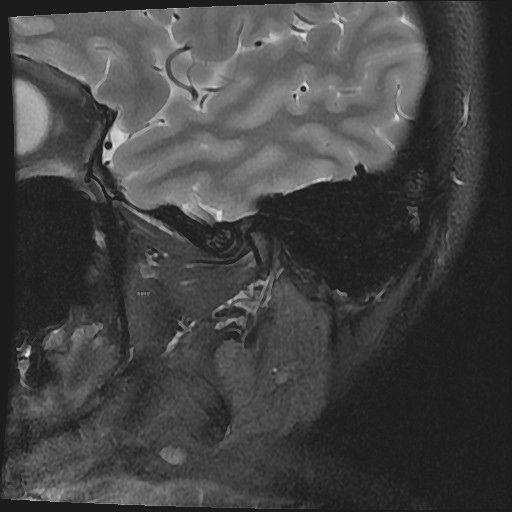

구강내과 턱 MRI 어느 사진이 우측? 좌측?인지 어떻게 보나요? 디스크 두꺼워짐 심한가요?ㅜ

구강내과 턱 MRI 사진 보는데 귀 위치가 다 똑같아서요

어느 사진이 우측? 좌측?인지 어떻게 보나요?

그리고 사진 상 디스크 두꺼워짐 심한가요?ㅜ

현재 사진만으로는 정확히 왼쪽이나 오른쪽이다 라고 할 수 없습니다. 이는 데이터 상의 reference가 필요하며 보통은 해당 부위가 질문자님 기준으로 좌측일 가능성이 가장 크나 이는 좌우 반전을 할 수 있기 때문에 무조건 좌측이라고 할 수 없습니다. 현재 개구시와 폐구시에 보았을 때 condyle (아래턱 부위의 일부)가 disc를 넘어가지 못하고 있으며 이러한 경우 개구제한이 있거나 넘어가더라도 소리가 나면서 넘어갈 수 있습니다. 일부 염증도 보이고 있으므로 내과적인 치료를 하셔야 할 것으로 보입니다.